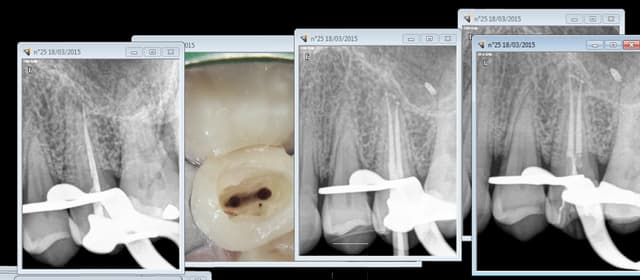

C'est con mais nos tarifs et prestations sont transparents ( gros bémol toutefois en ce qui concerne la qualité des soins, jamais controlée voir en PJ, seul le prix de la prothèse est pris en compte ) . On ne peut pas dire la meme chose des mutuelles. On ne peut pas les comparer, et donc les mettre en concurrence c'est ca l'arnaque !